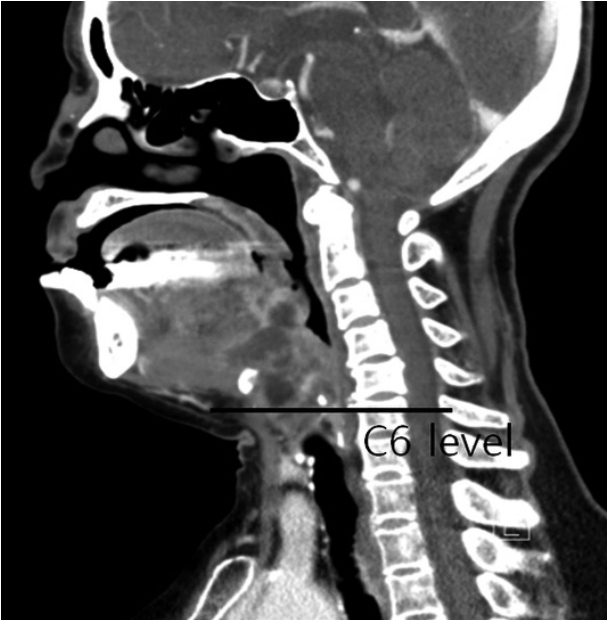

배농한 농양의 깊이 측정배농한 농양의 깊이를 CT의 시상면에서 측정하였다. 시상면 CT에서 농양의 하연에 수평으로 선을 그어서, 이에 해당하는 경추 위치로 정하였다(Fig. 2).

NotesAuthor Contribution Conceptualization: Myoung Su Choi. Data curation: Myoung Su Choi. Formal analysis: Dong Sik Chang. Investigation: Jun Lee, So Young Choi. Methodology: Myoung Su Choi. Project administration: Dong Sik Chang. Resources: Dong Sik Chang. Software: Myoung Su Choi. Supervision: Dong Sik Chang. Validation: Myoung Su Choi. Visualization: Myoung Su Choi. Writing—original draft: Myoung Su Choi. Writing—review & editing: Myoung Su Choi. Fig. 1.Enhanced CT scan revealed an ovoid abscess pocket involving the right parapharyngeal and paralaryngeal space, causing significant airway narrowing (upper). Incision and drainage of the abscess was performed with Evac Coblator (Arthrocare ENT) and endoscope via transoral approach (lower). Fig. 2.Measuring depth of the abscess at which the horizontal line of the lower margin of it meets the cervical vertebrae in CT. Table 1.Clinical characteristics of patients